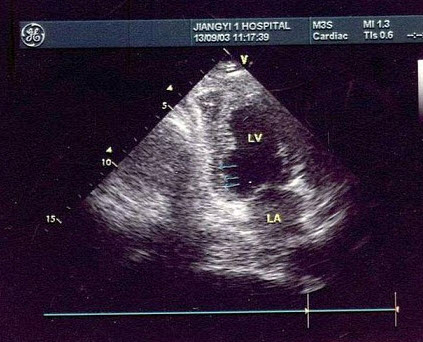

6、单项选择题

该病例最有可能诊断是()